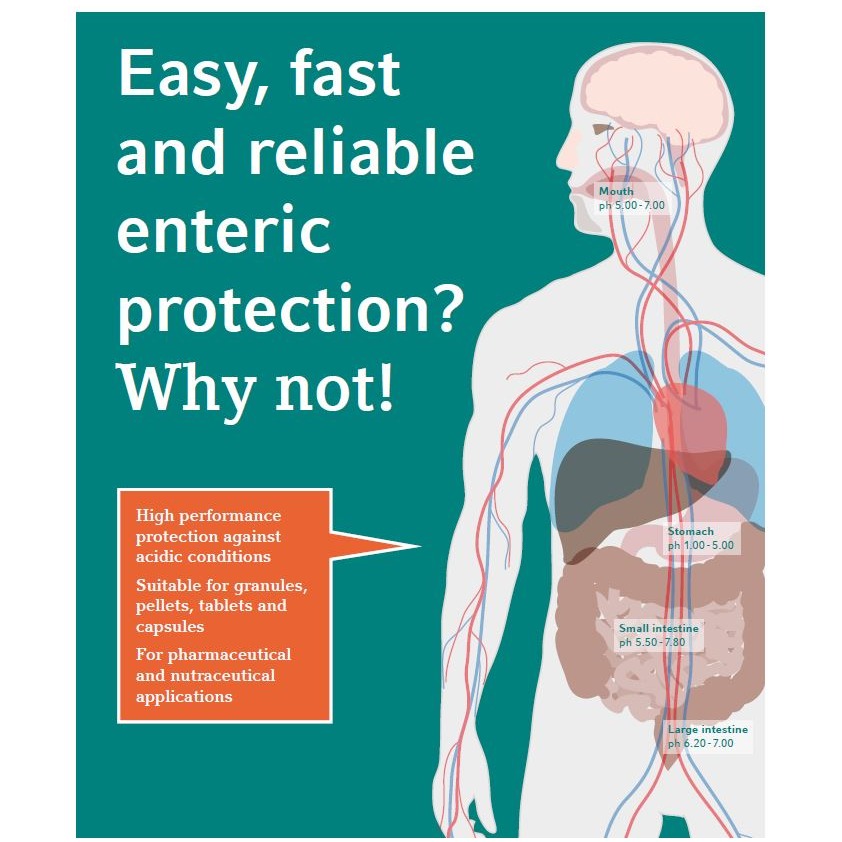

Product SERVICES

With a wide range of new customer services, we are a strong partner with innovative and customised full-service solutions to meet your specific needs.

Building on our expertise in high-value polymer films, we deliver innovative, partnership-driven solutions that go beyond products. Our offerin...